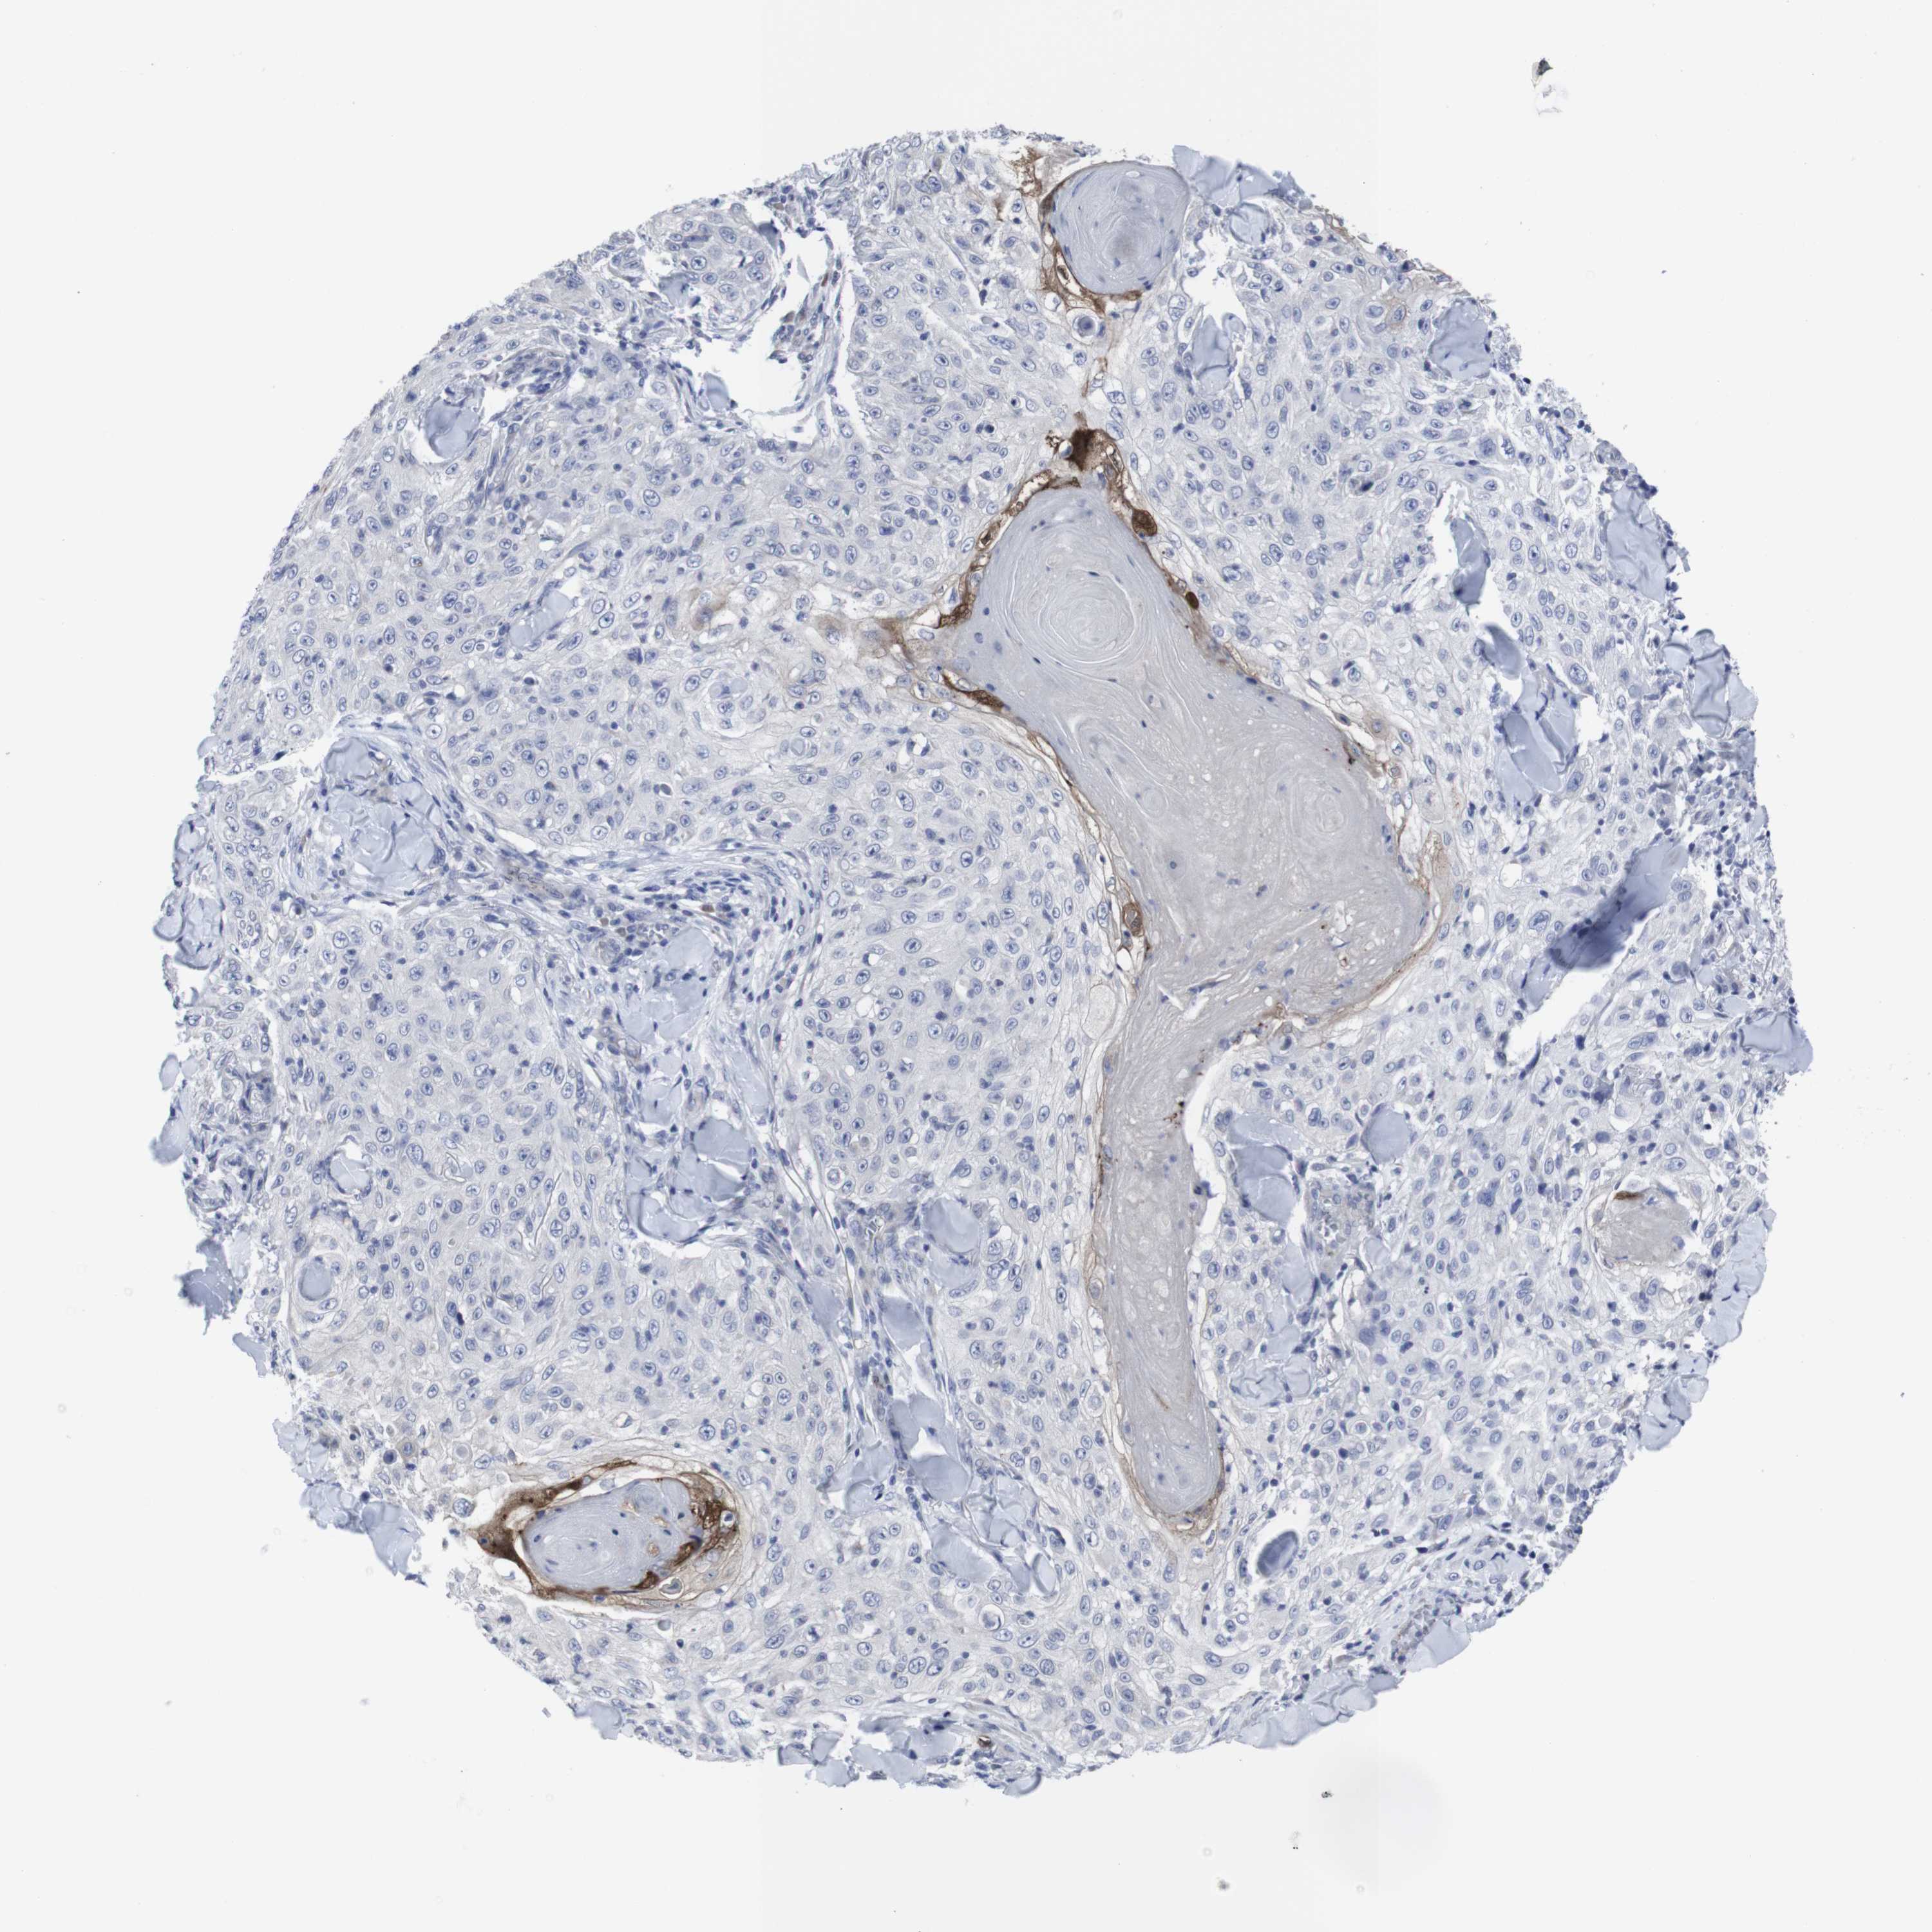

SKIN CANCER - Protein expressioni

A mouse-over function shows sample information and annotation data. Click on an image to view it in a full screen mode. Samples can be filtered based on level of antibody staining by selecting one or several of the following categories: high, medium, low and not detected. The assay and annotation is described here.

Each image is clickable and will lead to virtual microscopy that enables deeper exploration of all samples and also displays staining intensity scores, fraction scores and subcellular localization as well as patient and tissue information for each sample.

Antibody CAB040581

Adnexal tumor, benign